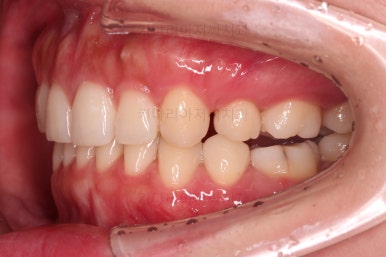

장치 부착 직후의 모습인데요.

장치가 어디있냐고요?

이번 환자분이 선택하신 장치는 인비절라인이라는 투명교정장치였기 때문에 치아에는 유심히 관찰해 보면 보이는 작은 치아색깔의 어태치먼트라는 버튼 이외에는 부착물이 없답니다.

저 상태로 투명교정장치를 빼고 끼면서 치아를 움직이게 됩니다.

필요한 발치, 급한 충치치료는 마무리된 상태이고요.